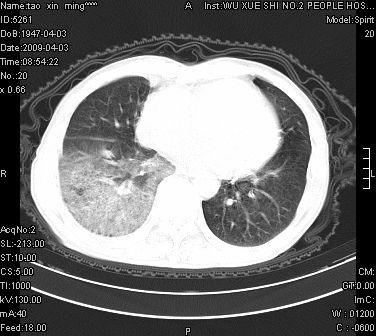

男.62.咯血.胸痛

是不是外伤的,看起来右侧肋骨骨折,右肺唑伤,右胸腔积血, 右肺背段可见一软组织肿块,边缘清晰,可以和中中央型肺ca合并

肺出血,周围型肺癌,右侧胸腔积液

右下周围型肺癌,右侧胸腔积。

右下周围型肺癌,右下肺出血,右侧胸腔积。

1)考虑右肺下叶周围型肺癌,并右肺下叶肺出血。2)右侧少量胸腔积液。

1)考虑右肺下叶周围型肺癌。2)右侧少量胸腔积液。

右下肺阴影,右胸腔少量积液。